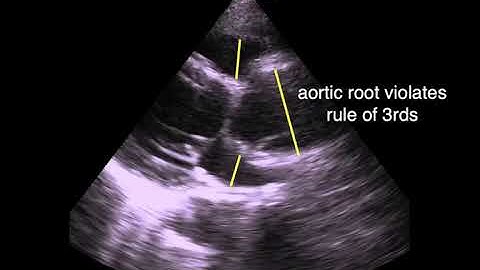

Semi-supervised Virtual Regression of Aortic Dissections Using 3D Generative Inpainting (Talk)